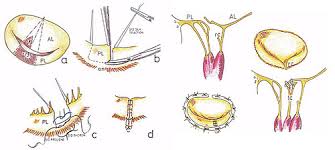

روش های زیر مورد استفاده قرار می گیرند:

- برداشت بافت اضافی و بازسازی لت صدم خورده یا منبسط شده دریچه

- حذف و برداشت رسوبات حلقه یا که لت دریچه

- مرمت و بازسازی رباط ها

- تعبیه یک حلقه مصنوعی یا از بافت کیسه قلب، جهت برقراری اندازه طبیعی حلقه دریچه

ترمیم دریچه میترال

جراحی دریچه میترال در سال های اخیر بطور فزاینده تبدیل به یک عمل ترمیمی-بازسازی با حفظ ساختار طبیعی دریچه شده است.

حفظ دریچه و سازه های زیرین آن باعث عملکرد بهتر بطن چپ و حفظ توان و نیروی بیمار می گردد. همزمان دیگر نیازی به استفاده از داروهای ضد انعقلدی نیست و از عواقب احتمالی همچون خونریزی و ترومبوامبولی اجتناب می شود. عمل های ترمیم دریچه نیاز به تجربه و تبحر زیاد دارد، ولی در دستان جراحی که به آن مسلط است باعث بهبود کیفیت زندگی بیمار می باشد.